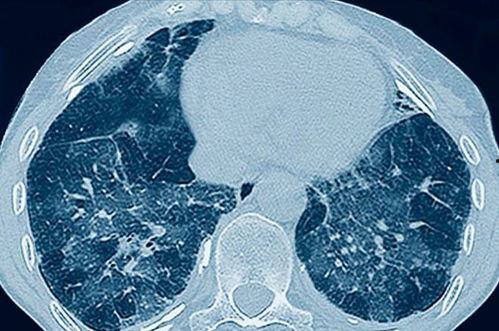

首先,让我们来欣赏一下肺呼吸视频的精彩片段。视频中,你可以看到肺部随着呼吸的起伏,就像一个巨大的气球,时而膨胀,时而收缩。这个过程就像一场奇妙的魔术表演,让人不禁感叹大自然的神奇。